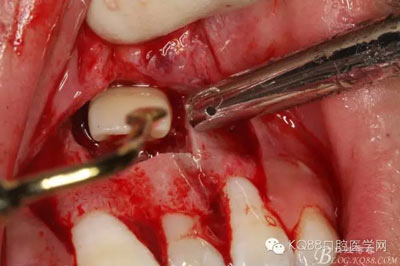

圖5.局部無痛麻醉下。行唇側(cè)齦溝內(nèi)切口

圖6.雙側(cè)垂直附加切口,形成梯形瓣

圖7.翻瓣、注意是全厚瓣。